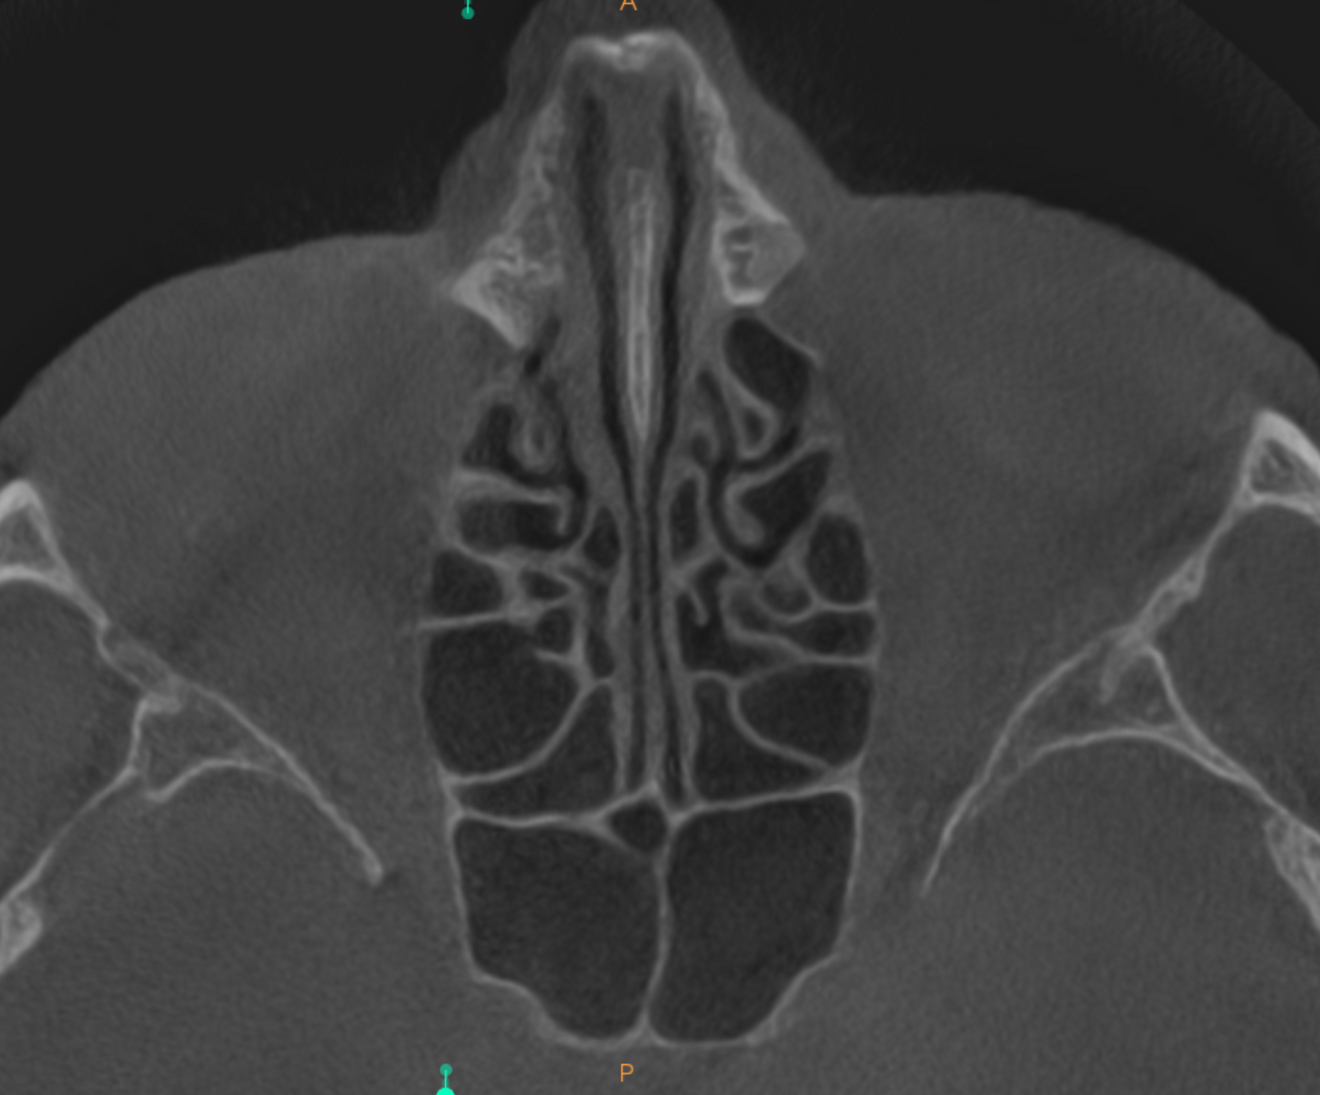

Figs. 1a & b: Initial small-volume CBCT scan, panoramic view (a) and cross-section of tooth #17 (b).

The 61-year-old male patient wanted to have his missing maxillary right teeth replaced with implants. After examination by an implantologist, he was referred to our dental office for further dental treatment because of the findings of a small-volume CBCT scan taken: advanced inflammation and bone loss were visible in the periodontal tissue of the maxillary right second molar and severe maxillary sinusitis was observed (Figs. 1a & b).